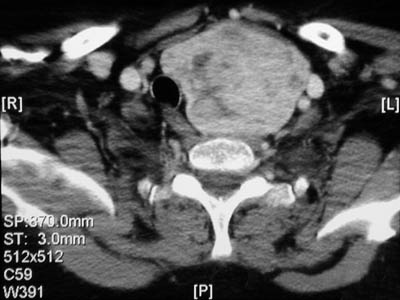

| The series of CT scans seen here demonstrate a large but asymmetric nodular goiter which involves the left lobe and produces marked displacement of the trachea to the right. In the views below, the goiter extends into the lower neck and down into the upper chest. Thus, a substernal location for a goiter is not impossible. |